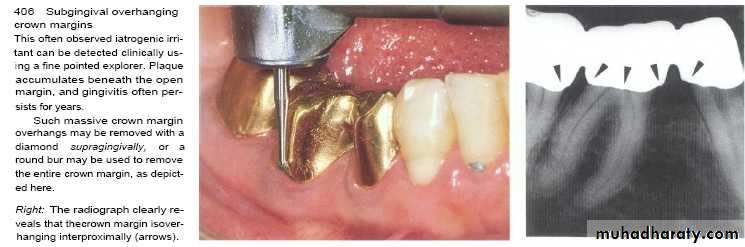

• Overhanging margins induce plaque accumulation & change

• the environment that allows growth of pathogenic bacteria &

• inhibit patient access to remove plaque.

4- Inadequate marginal fitness of restoration.

Subgingival margins typically have a gap of 20 to 40 microns between the margin of the restoration and the unprepared tooth.

Marginal fit has close relation with an inflammatory response in the periodontium.

It has been shown that the level of gingival inflammation can increase with increasing level of marginal opening.

Margins that are significantly open are capable of harboring large numbers of bacteria and may be responsible for the inflammatory response .